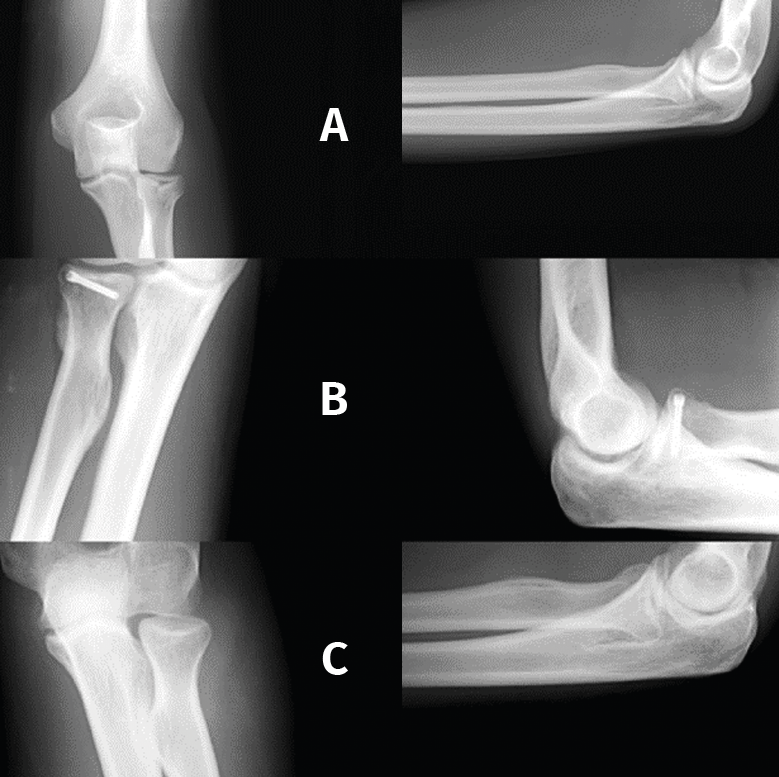

Las osificaciones heterotópicas limitan la movilidad, especialmente en las fracturas de la cabeza del radio por su situación anatómica y la complejidad del mecanismo de pronosupinación (Figura 1).

Figura 1. Calcificación heterotópica posfractura de la cabeza del radio. A: imágenes de la fractura; B: calcificación heterotópica en cuello; C: imagen tras la exéresis.